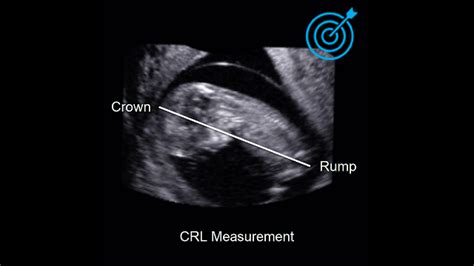

Understand your baby's development with our guide to Crown Rump Length (CRL). Learn how this essential ultrasound measurement determines gestational age, confirms an accurate due date, and tracks fetal growth during your first trimester. Discover why the CRL is the most reliable clinical tool for early pregnancy dating and ensuring your baby is meeting key developmental milestones.